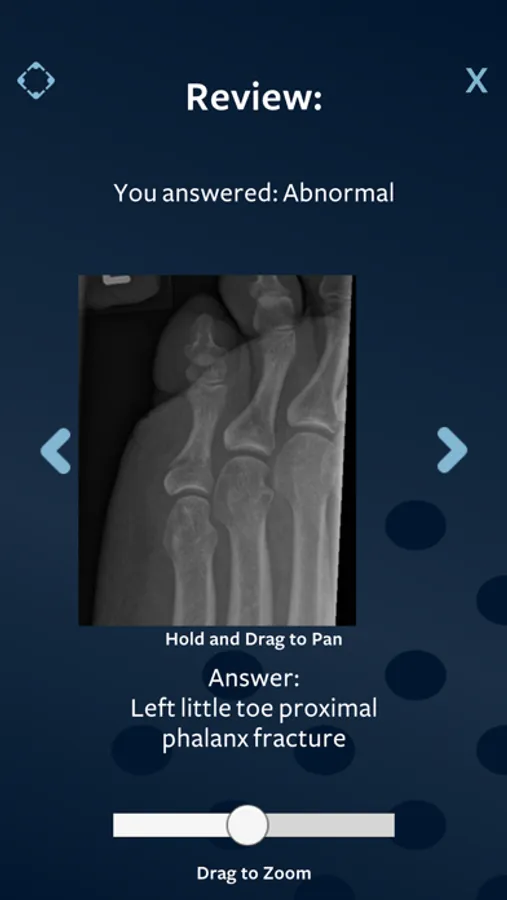

Find the Normals

This game is aimed at helping you become more confident at spotting normal x-rays.

The danger with calling a normal x-ray abnormal, is that it can lead to excessive investigation and patient anxiety, as well as the risk of exposing the patient to unnecessary radiation.

The skill of picking up normal x-rays is tested during the Rapid Reporting section of the Final Part B examinations of the FRCR (Fellowship of the Royal College of Radiologists).

Simply choose the difficulty of X-Rays you’d like to practice and get instant feedback on whether you got it right or wrong. You can review your answers after the timer runs out and see whether you picked up the normals. You also get to see the diagnoses of the abnormal x-rays. Try to improve on your results to become faster and more accurate.

This game will help with preparation for the FRCR 2B Rapid Reporting Exam but if you need more rapid reporting practice in a platform that simulates the examination, visit the Revise Radiology website.